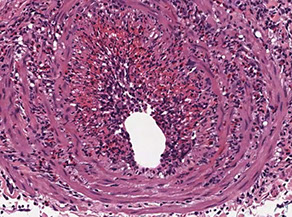

Temporal (Giant cell) aortitis/arteritis

MC vasculitis in large (and medium-sized) arteries

- usually affects branches of the carotid artery (ie temporal a.) in elderly females

- affects large and medium sized branches of the aorta c predilection for the extracranial branches of the carotid artery

Micro: Fragmented elastic fibers, giant cell / granulomatous (macros and lymphos) response and intimal thickening which reduces lumen

- giant cells not required for temporal arteritis (in ~75%), only destruction of internal elastica with inflammation

-false negatives due to focal distribution and steroid tx before biopsy (3-5 cm); polymyalgia rheumatica (muscle pain)

Dx: Temporal a. bx

Tx: high-dose steroids (do not wait for bx results to tx - Emergency!!)

Giant cell arteritis of the breast. The vessel wall has been replaced by granulomatous inflammation. The process has compressed the vessel lumen to near-complete obstruction. A giant cell is shown in this field. B, Giant cell arteritis of the breast. Granulomatous inflammation and fibrinoid necrosis are shown within the wall of this vessel. C, Giant cell arteritis of the breast. The special elastin stain highlights the fragmentation of the internal elastic

lamina in this vessel (hematoxylin-eosin, original magnifications320 [A and B]; original magnification320 [C]).